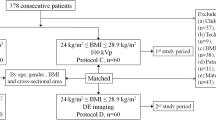

The inclusion criteria included patients with known or suspected liver lesions, chronic hepatitis, or liver cirrhosis based on a treatment history, prior imaging examination, or abnormally increased tumour marker (a-fetoprotein >11 ng/mL or carcinoembryonic antigen > 5 ng/mL) level and was scheduled for clinically indicated multiphase liver CT. Clinical exclusion criteria were patients younger than 18 years of age, pregnant or lactating, had history of an allergic reaction to iodinated contrast media, or compromised renal function (estimated glomerular filtration rate <30 mL/min/1.73 m2). Thirty-four (17.5 %) of the 194 patients were excluded for the following: 10 patients had advanced liver cirrhosis defined as Child-Pugh class C; there was a technical failure during contrast injection for six patients; 18 patients declined after reviewing the informed consent.

Finally, 160 patients were recruited between February and May 2015. Morphologic data (weight, height, and body mass index [BMI, calculated as the weight in kilograms divided by height in meters squared]) were recorded. Body weights in all patients prior to CT examination were measured to tailor the amount of contrast media of their individual needs.

For each patient, the CTDIvol (mGy) and dose-length product (DLP, mGy · cm) values were recorded in protocols A and B on the AP images. Radiation dose for the PVP scan acquired during a single breath-hold by helical scan of the liver using the same scanning parameters as that for the AP scan, was not included in the analyses. The estimated effective radiation dose (mSv) was obtained by multiplying the DLP by a conversion factor of 0.015 for abdominal examination, as recommended by the International Commission on Radiological Protection (ICRP) publication 103[31]. To analyze effective radiation dose distribution according to patient sizes, four groups were categorized according to their body mass indices (BMI) (less than 18.5 kg/m2, underweight; between 18.5 and 23.9 kg/m2, normal BMI; between 24 and 28.9 kg/m2, overweight; and 29 kg/m2 or greater, obese)[32]. The correlations between BMI and recommended CTDIvol with ASIS technique were calculated.